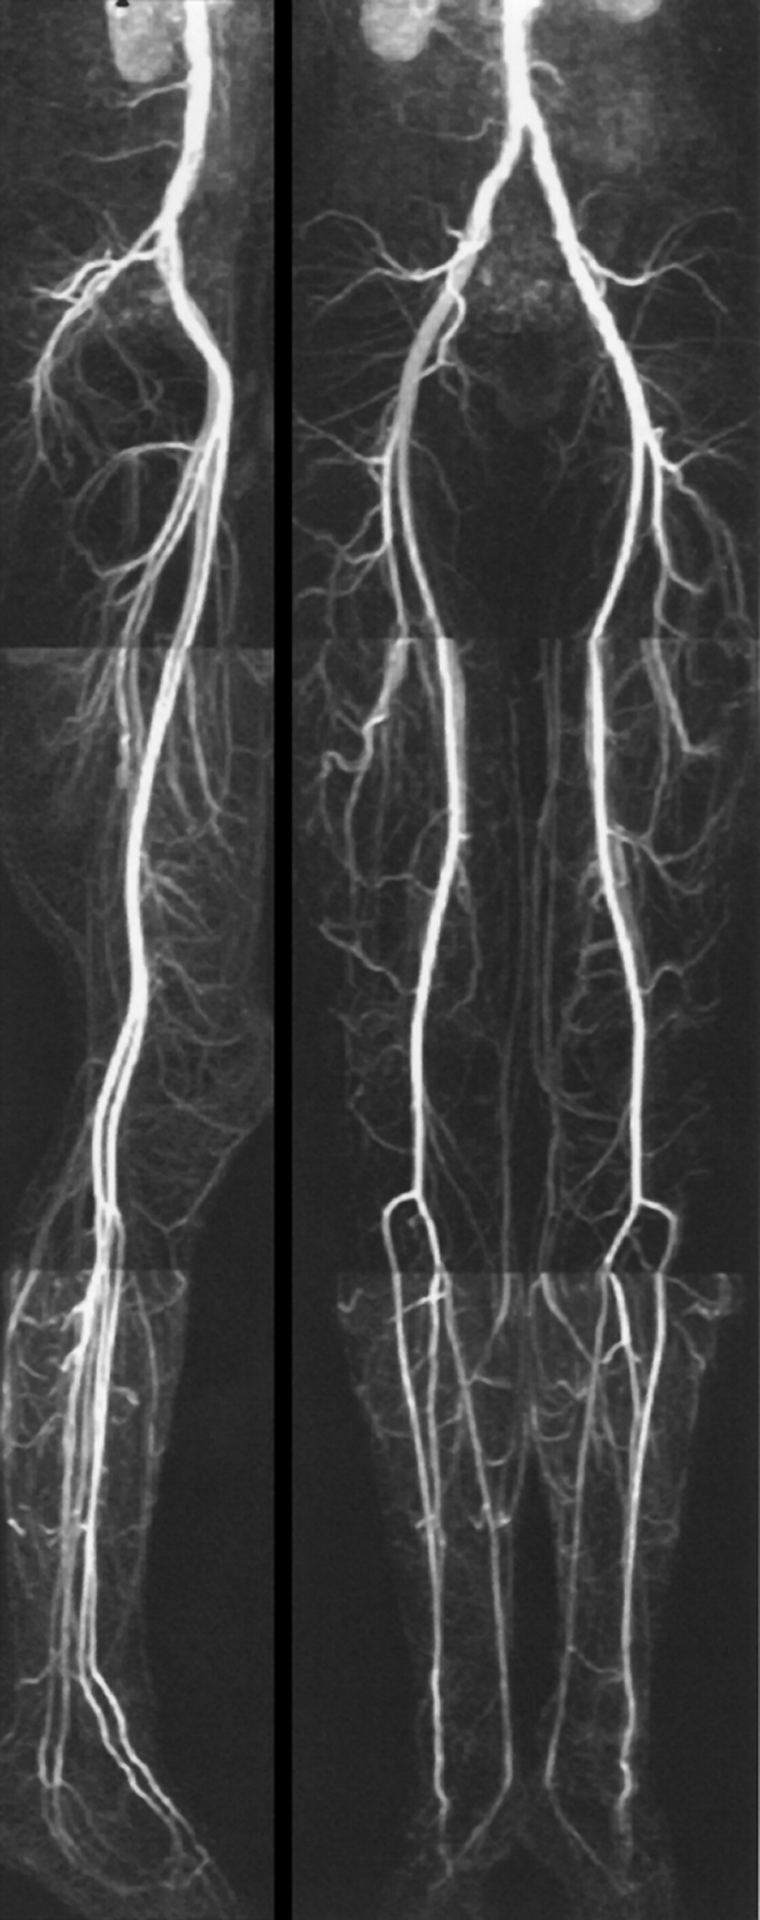

In combination with mechanical de­vi­ces the entire peripheral vascular system can thus be examined after a single contrast agent injection (Fi­gu­re 14-22). The com­bi­­na­tion of ra­­pid automatic table movement and automatic injection and follow-up of the bolus allows mul­ti­ple suc­ces­si­ve acqui­sitions.

Figura 14-22:

Moving-bed CE-MRA of the pelvis and legs.